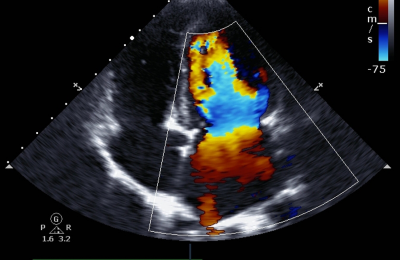

Pulsed-wave Doppler allows for real-time analysis of blood flow. The next innovation was color Doppler, which overlays color information onto the two-dimensional grayscale image, encoding the direction and average velocity of the flow. This development has been fundamental for the diagnosis of arterial stenosis, venous thrombosis, valvular insufficiency, and also in obstetrics, for the study of fetoplacental circulation.